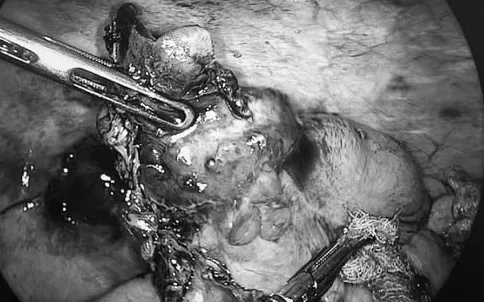

Tuy nhiên, trong quá trình phẫu thuật, ekip mổ phát hiện ruột thừa có khối u bất thường, nghi ngờ tổn thương ác tính. Trước tình huống này, các bác sĩ đã hội chẩn ngay trong mổ và quyết định chuyển phương án phẫu thuật, tiến hành cắt đoạn đại tràng phải nhằm bảo đảm nguyên tắc điều trị triệt để theo chuyên khoa ung bướu.

Ca phẫu thuật được thực hiện an toàn, đúng quy trình kỹ thuật. Kết quả giải phẫu bệnh sau mổ xác định bệnh nhân mắc ung thư ruột thừa. Sau phẫu thuật, bệnh nhân hồi phục tốt, tình trạng sức khỏe ổn định và tiếp tục được theo dõi, điều trị theo phác đồ phù hợp.